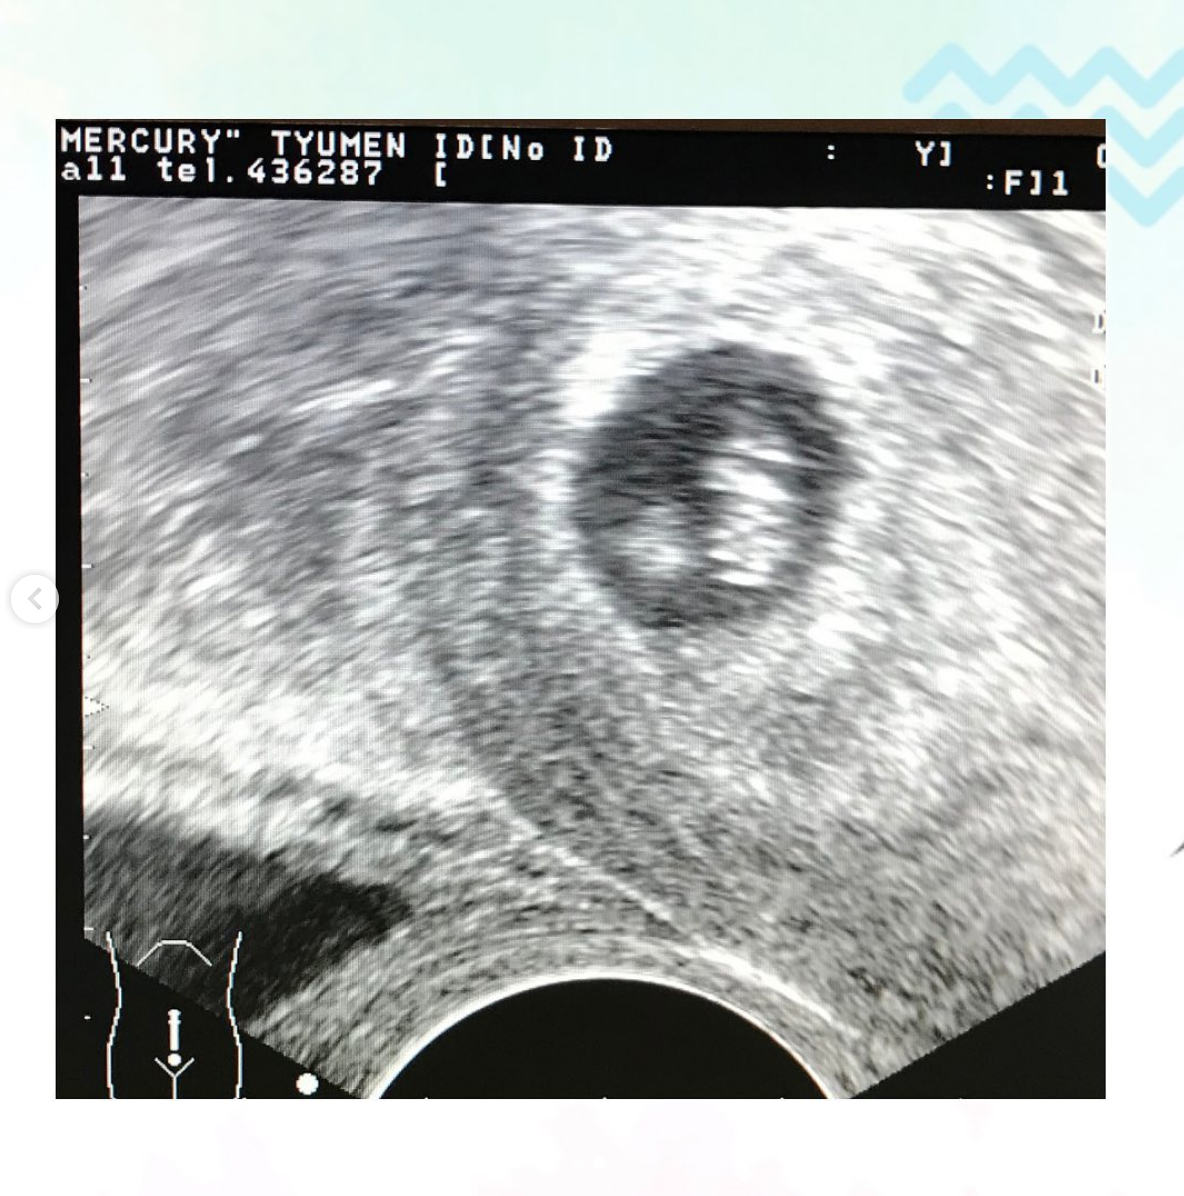

⠀⠀ «А я к вам на УЗИ. Что-то задержка опять у меня. Наверное, нужно поменять лечение», - говорит она мне.

⠀ ⠀ Как думаете, что я увидела на УЗИ?

⠀⠀Да.Да.Да. Это была беременность. Уже восемь недель. И сердечко уже билось.

⠀Наталья плакала, лёжа на кресле, а я вереща от счастья, успевала фотографировать нашего малыша.